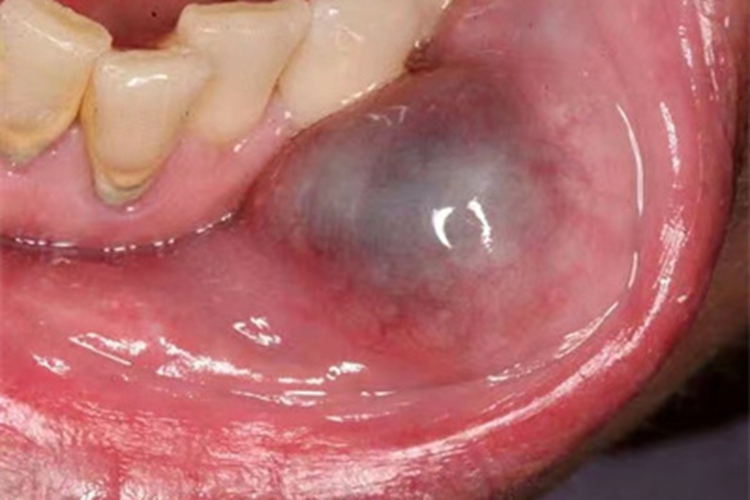

黏液腺囊肿可见局部出现囊肿,呈半透明状,颜色为浅蓝色,有一定弹性。

黏液腺囊肿可见囊肿表现,囊肿位于黏膜下,表面有薄层黏膜,呈半透明、浅蓝色的圆形小泡,质地柔软有弹性。囊肿易被咬破,囊腔内可有蛋清样透明黏液流出,此时囊肿消失。